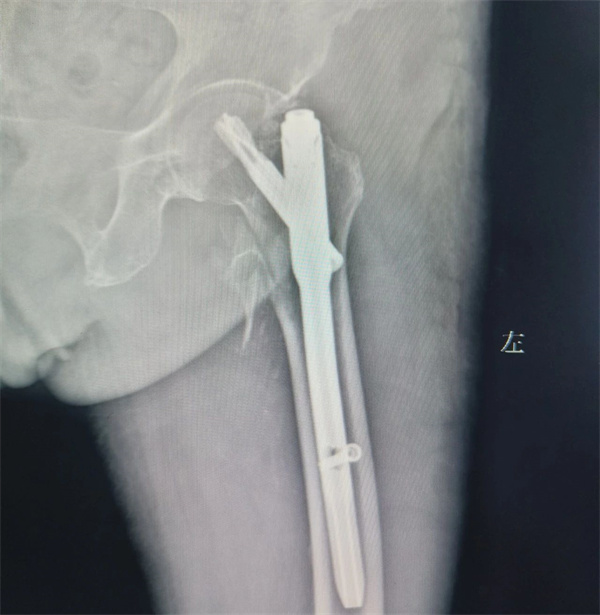

入院后,骨一科创伤团队精心制定了详尽的治疗方案,考虑到如果继续推迟林奶奶的手术,会导致坠积性肺炎、心脑血管意外、肺部感染等风险成倍增加。创伤团队一方面结合影像学资料及患者的身体条件,明确了PFNA手术的适应症,另一方面召集麻醉科、影像科、呼吸内科等多科室专家进行MDT联合会诊评估手术风险,采取积极的抗炎,输血,补液,预防深静脉血栓等措施,为手术创造条件,同时详细地向患者及家属介绍了手术如何操作,微创手术的优势以及术中术后会出现哪些情况和相关应对措施,消除了患者及家属的顾虑。

7月17日,在医院手术室和麻醉科配合下,创伤团队高勇、张万泉两位副主任医师顺利地为林奶奶实施了PFNA手术,在微创手术下,林奶奶腿部仅有3个小切口,耗时不到1小时,手术非常成功。术后又联合呼吸内科、心内科、ICU等多科室专家会诊,为林奶奶设计针对性强的治疗方案。术后1周,林奶奶就可以下床活动了,林奶奶及其家属的脸上都露出了满意的笑容,他们都表示,是市二医院脊柱创伤团队给这位耄耋老人再次带来了新生。